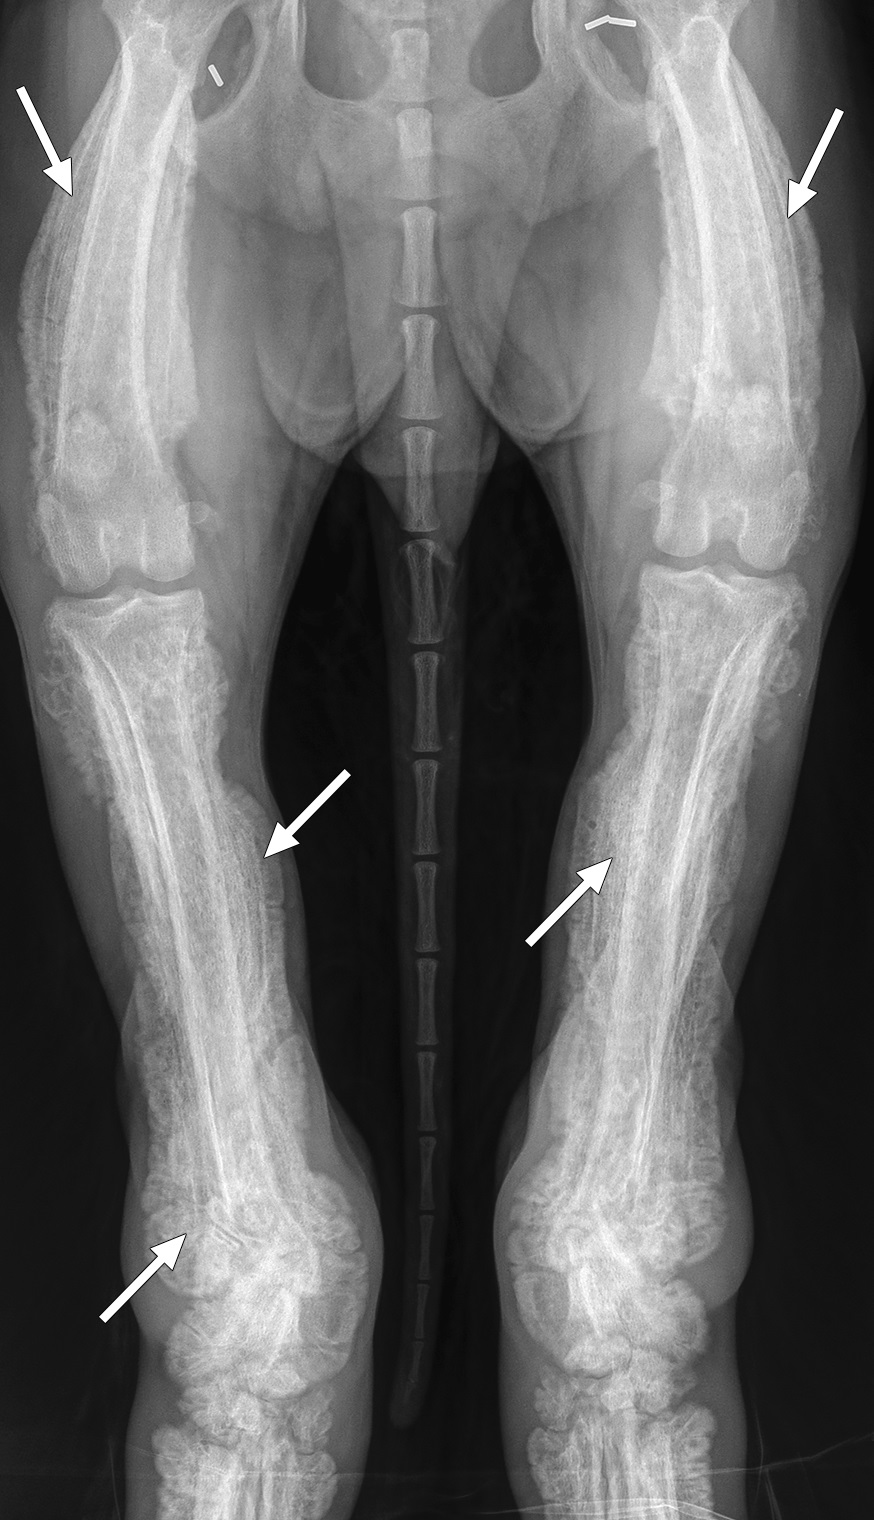

Bilateral symmetrische hochgradig spikula- bis palisadenähnliche periostale Reaktionen an den langen Röhrenknochen.

Die hypertrophe Osteopathie ist ein seltenes paraneoplastisches Syndrom, das bei etwa 3% der Hunde auftritt und durch proliferative periostale Reaktionen in den diaphysären Bereichen der Röhrenknochen gekennzeichnet ist [1] , [2] . Eine lokale Hypoxie, Wachstumsfaktoren (VEGF, PDGF) und eine chronische Entzündung werden als Ursache diskutiert [3] . Auch bei nicht tumorösen Veränderungen im Thorax kann es zu einer hypertrophen Osteopathie kommen.